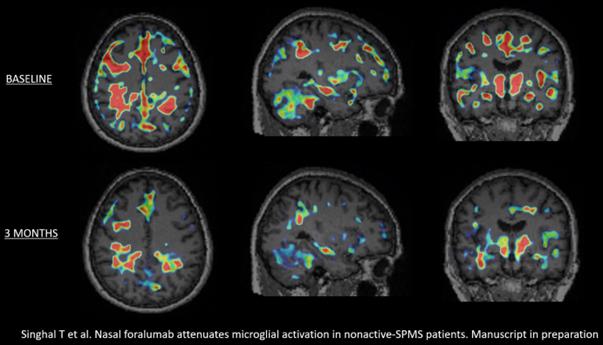

Tarun Singhal, M.B.B.S., M.D., Director of PET Imaging Program in Neurologic Diseases, associate neurologist and nuclear medicine physician at Brigham and Women’s Hospital, a founding member of Mass General Brigham Healthcare System, and Assistant Professor of Neurology at Harvard Medical School, commented, “After review of the baseline and 3-month PET scans of the latest cohort of 4 Expanded Access patients, I have determined that 3 out of the 4 patients had a reduction in the microglial PET signal. An example of this can be seen in the graphic below, titled, “Figure 1”, showing the deactivation of this signal in patient EA6. When combined with my assessment of the first 2 Expanded Access patients, a total of 5 out of the 6 had a reduction in qualitative microglial PET signal, which appears to be clearly more significant than what we have identified in our test-retest assessments. I look forward to studying more patients, with full quantitation, and particularly, the next 4 patients in the Expanded Access program to see if this finding is replicated. We are preparing to submit the important results from this trial for publication.”

Figure 1.

Howard L. Weiner, M.D., Chairman of Tiziana’s Scientific Advisory Board and Co-Director of the Ann Romney Center for Neurologic Diseases at Brigham and Women’s Hospital, a founding member of Mass General Brigham Healthcare System, stated, “To see a reduction in microglial activation in 5 out of 6 na-SPMS patients in only 3 months is extraordinary. This finding is even more remarkable because all of the 6 expanded access patients’ na-SPMS had clinically regressed on ocrelizumab treatment. I am excited to follow this program to see if the improvement in the 3-month PET scans will translate to clinical improvement in the coming months.”